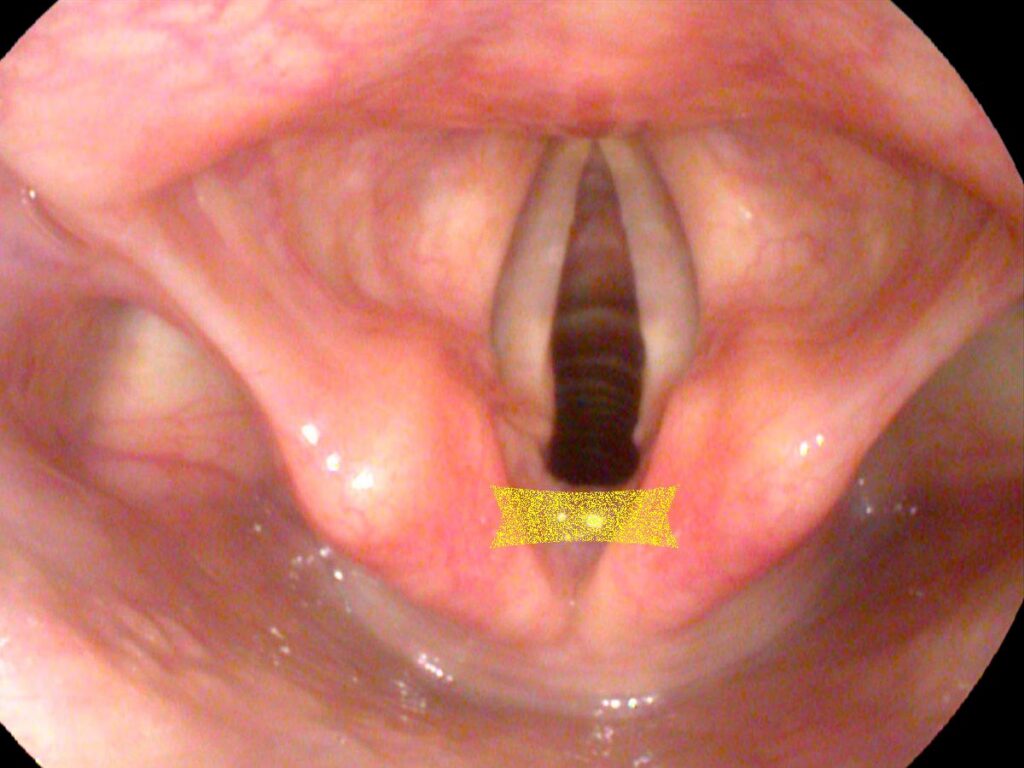

Because the IA muscles connect in the midline, this is one muscle where there seems to be cross innervation or nerve input from the opposite side. So even when there is complete paralysis of one side of the larynx, the IA muscle on the injured side may still function because of this cross innervation. In this situation, on endoscopy we may see a twitch of the arytenoid of an otherwise apparently completely paralyzed vocal cord due to innervation from the opposite IA muscle.

- A twitch can reveal partial function — a visible arytenoid twitch in an otherwise paralyzed cord may signal intact cross innervation from the contralateral IA.